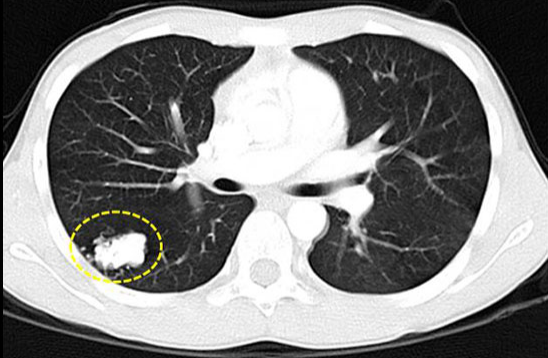

图文教你看懂恶性肺结节的ct表现_肺部结节 好大夫在线

肺部磨玻璃结节的克星1024ct靶扫描

这些结节不是肿瘤是正常的肺部结构

肺部结节